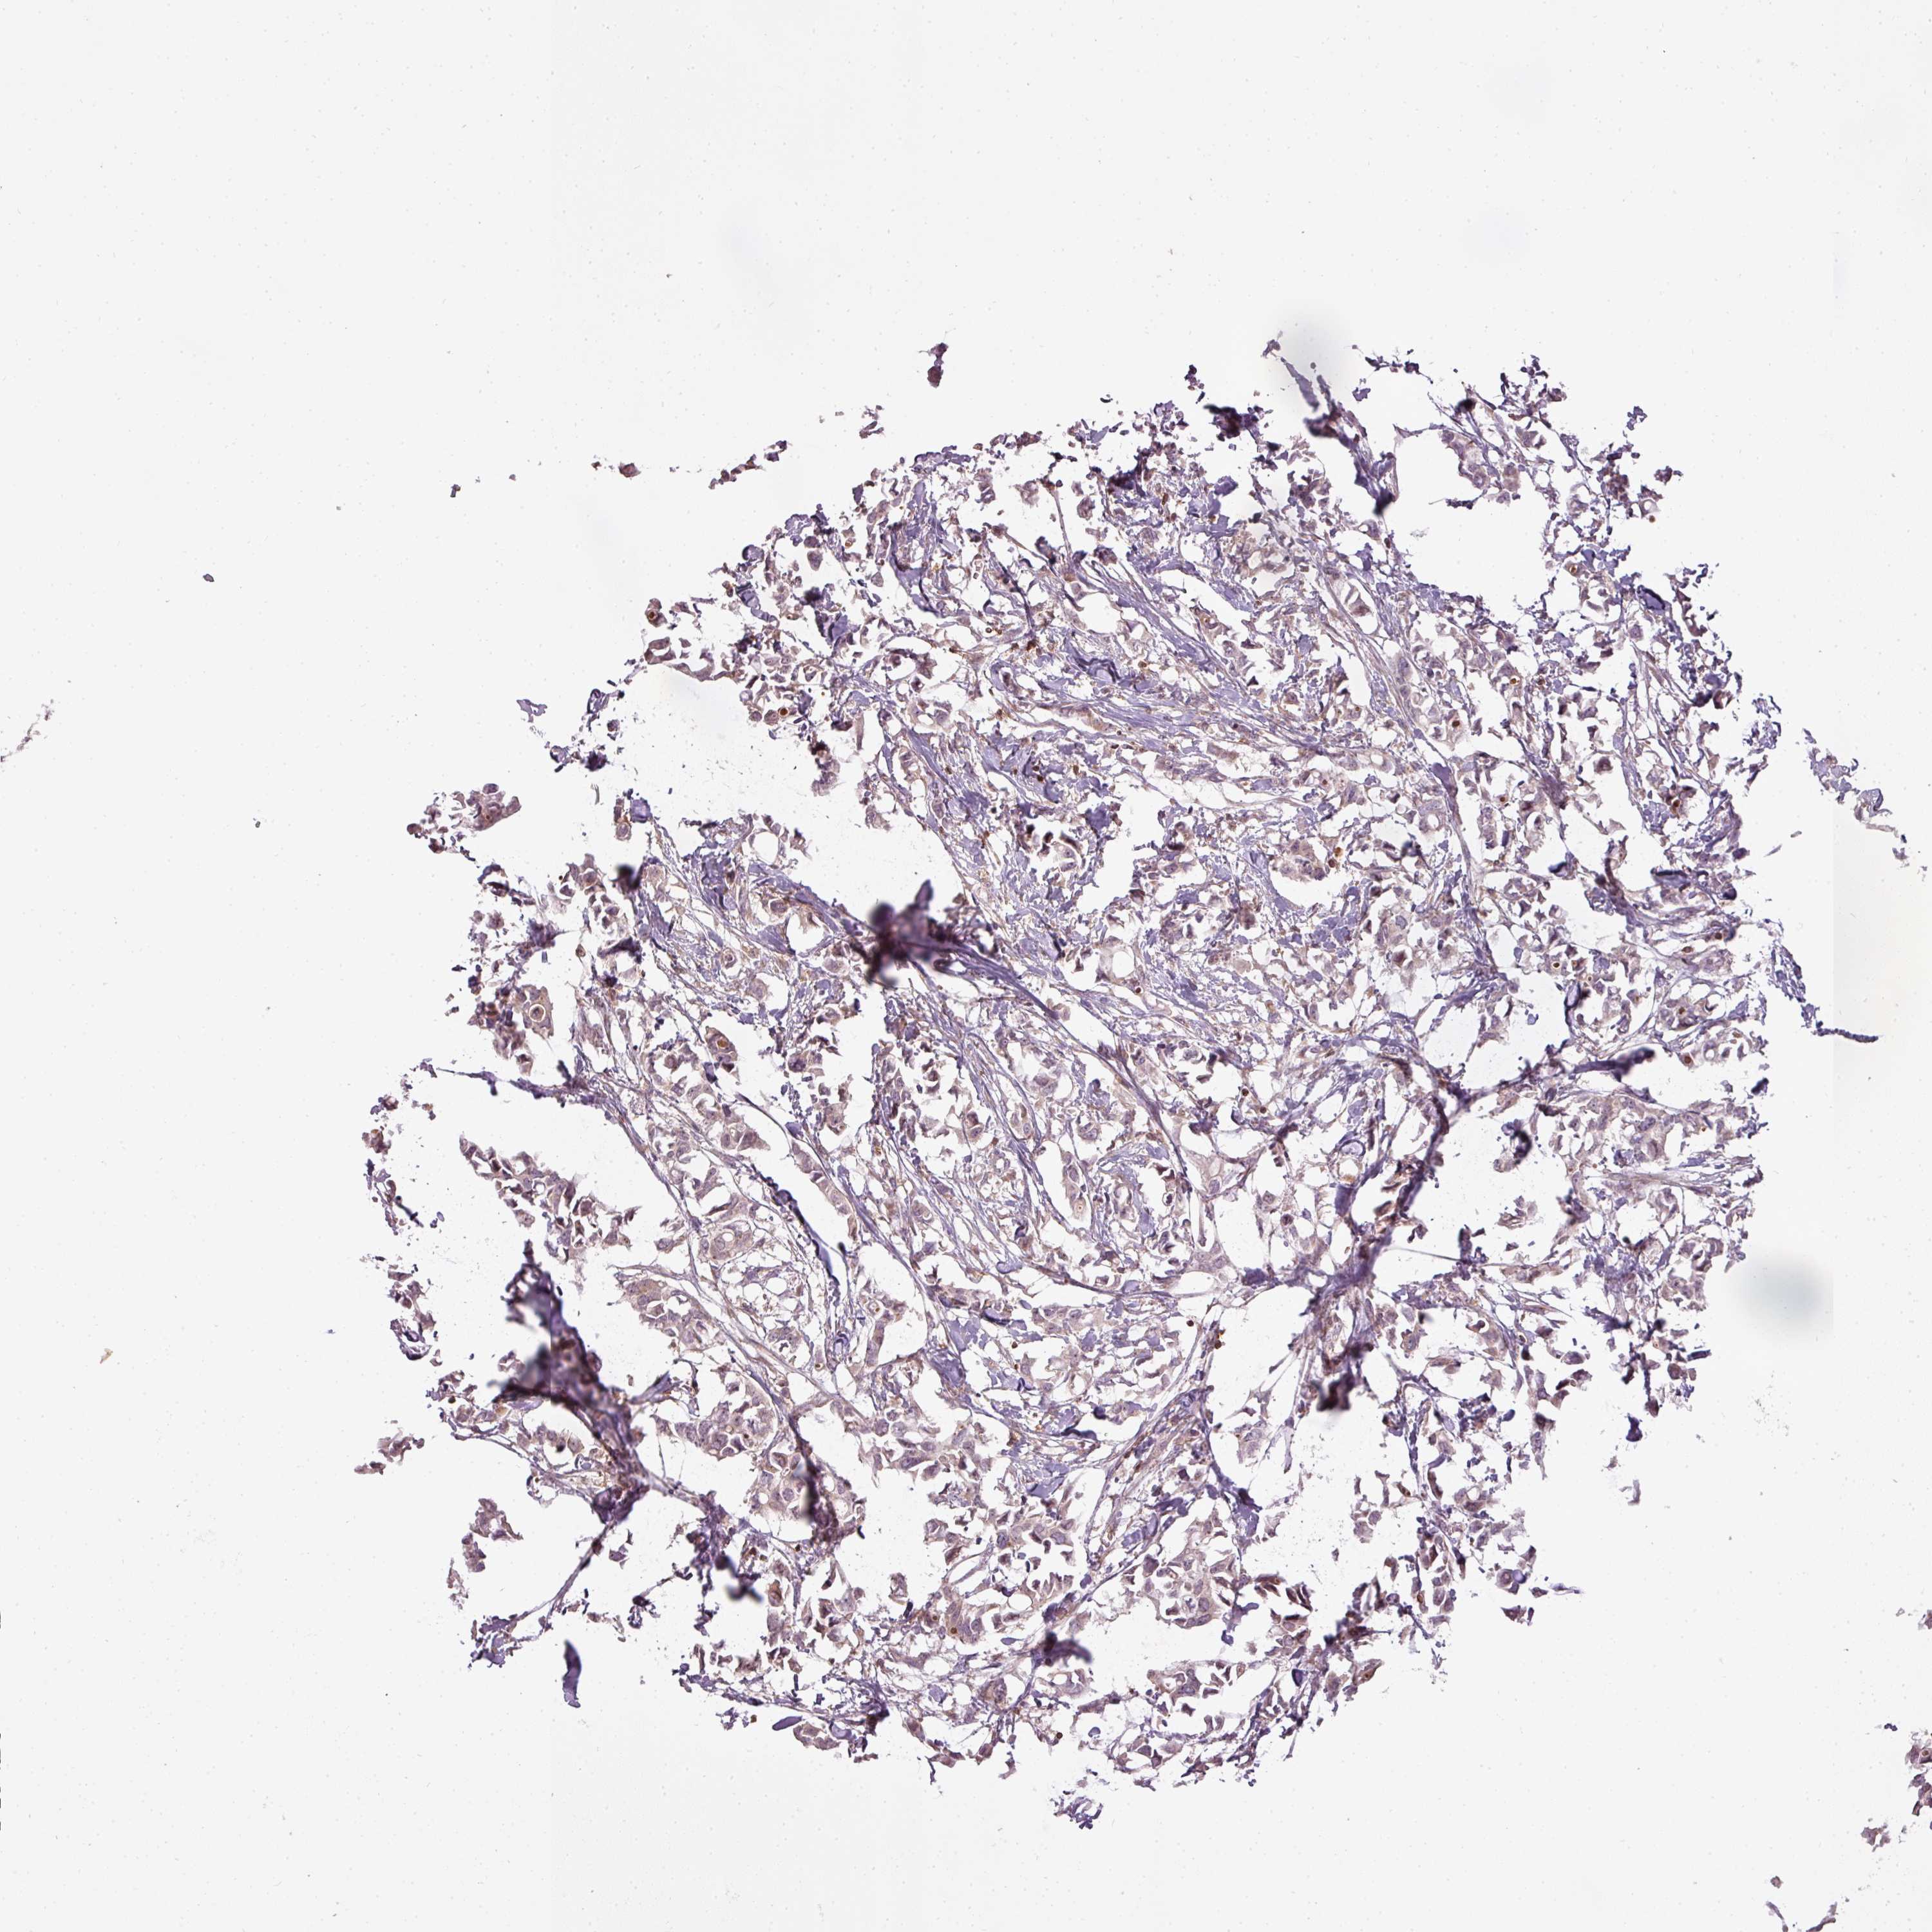

BRCA TCGA BRCA VALIDATION PROTEIN EXPRESSION